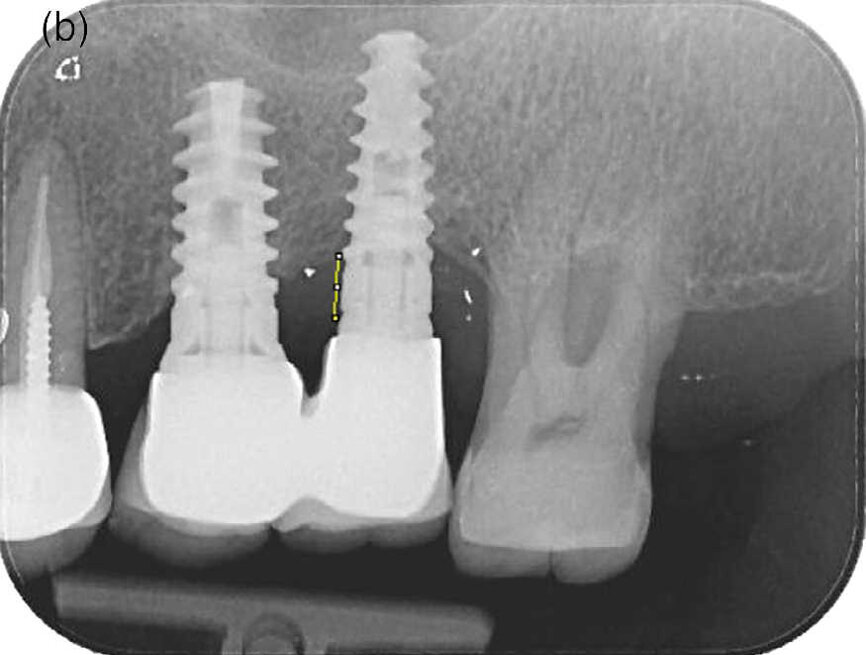

- La hauteur d’os (BL) a été mesurée entre la connexion implant-pilier et le fond du défaut osseux par un examinateur (O.G.), au début de l’étude et à T2, à l’aide d’un logiciel de traitement et d’analyse d’images (logiciel ImageJ, programme de traitement d’image écrit en Java, développé par les NIH [National Institutes of Health], Bethesda, Etats-Unis) (Fig. 2). Dans chaque radiographie, la longueur de l’implant fournie par le fabricant a été utilisée pour étalonner les mesures ≪ apico-coronaires ≫. La distance jusqu’au tissu osseux coronaire a été mesurée au niveau de la face mésiale et de la face distale de l’implant.

Des radiographies per apicales prises avant le traitement et 12 mois après le traitement n’étaient disponibles que pour un nombre limite d’implants (12 dans le groupe P et 15 dans le groupe M). L’analyse radiographique des mesures de hauteur osseuse n’a pas montré de différences statistiquement significatives entre les deux modalités de traitement (données non présentées/données sur fichier).